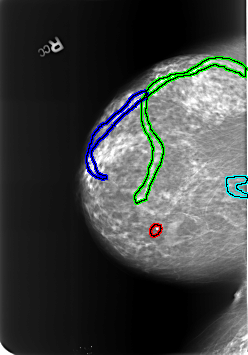

B_3239_1.RIGHT_CC

FILE: B_3239_1.RIGHT_CC.OVERLAY

TOTAL_ABNORMALITIES 4

ABNORMALITY 1

LESION_TYPE CALCIFICATION TYPE LUCENT_CENTER DISTRIBUTION N/A

ASSESSMENT 2

SUBTLETY 4

PATHOLOGY BENIGN_WITHOUT_CALLBACK

TOTAL_OUTLINES 1

BOUNDARY

ABNORMALITY 2

LESION_TYPE CALCIFICATION TYPE VASCULAR DISTRIBUTION N/A

ABNORMALITY 3

ABNORMALITY 4